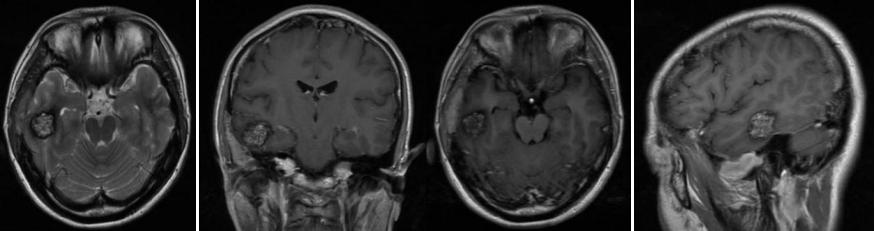

头部MRI示:右侧颞叶占位性病变合并出血改变